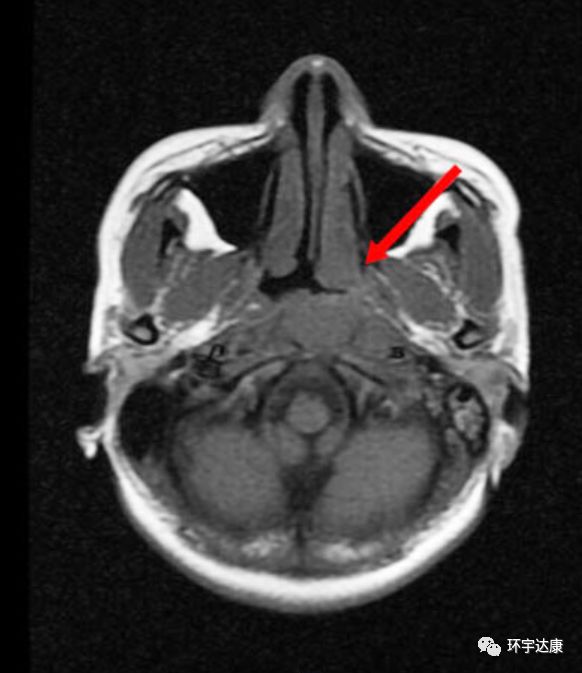

广东的吴女士在2013年7月出现左耳听力下降及左上颈明显肿大淋巴结,本以为是炎症,结果去医院检查后才被确诊为:非角化性癌,分化较差,鼻咽腔肿瘤侵润咽旁和颅底。双侧淋巴结转移。分期为:T3N1M0。

经过多西他赛+铂类化疗联合放疗后,病灶都有了明显的缩小。

不幸的是,2015年2月,复查结果显示,左侧鼻腔壁肿瘤局部复发。因为之前已经接受过了放疗,所以复发后吴女士可选的治疗方案很少。

再经过会诊后,吴女士了解到质子可以治疗复发的肿瘤,于是,吴女士选择了去国外接受质子质子治疗。

治疗期间,吴女士唾液分泌、皮肤、甲状腺无显著影响。治疗后MRI显示鼻咽左侧壁的局部复发已经明显缩小。两个月后吴女士开始正常上班。目前随访,病情处于稳定状态。